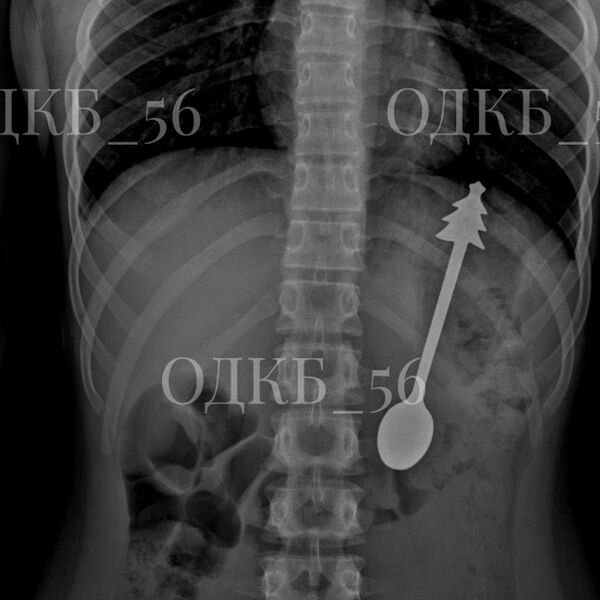

В Оренбургской области ребенок случайно проглотил 14-сантиметровую ложку

Врачи в Оренбургской области достали 14-сантиметровую ложку из желудка ребенка

Врачи извлекли 14-сантиметровую ложку из желудка ребенка в Оренбургской области. Об этом сообщила пресс-служба регионального министерства здравоохранения на странице в социальной сети «ВКонтакте».

По данным ведомства, несовершеннолетний случайно проглотил ложку, после чего его срочно госпитализировали. Бригада скорой помощи доставила ребенка в детскую больницу, где ему сделали рентген органов брюшной полости. В результате выяснилось, что инородное тело находится в желудке.

«В экстренном порядке проведено <...> эндоскопическое удаление инородного предмета — металлической ложки длиной 14 см. Постманипуляционный период протекал без осложнений», — говорится в заявлении.

Публикация дополнена фотографиями извлеченной из ребенка ложки. На кадрах видно, что на конце ручки столового прибора находится фигурка елки.